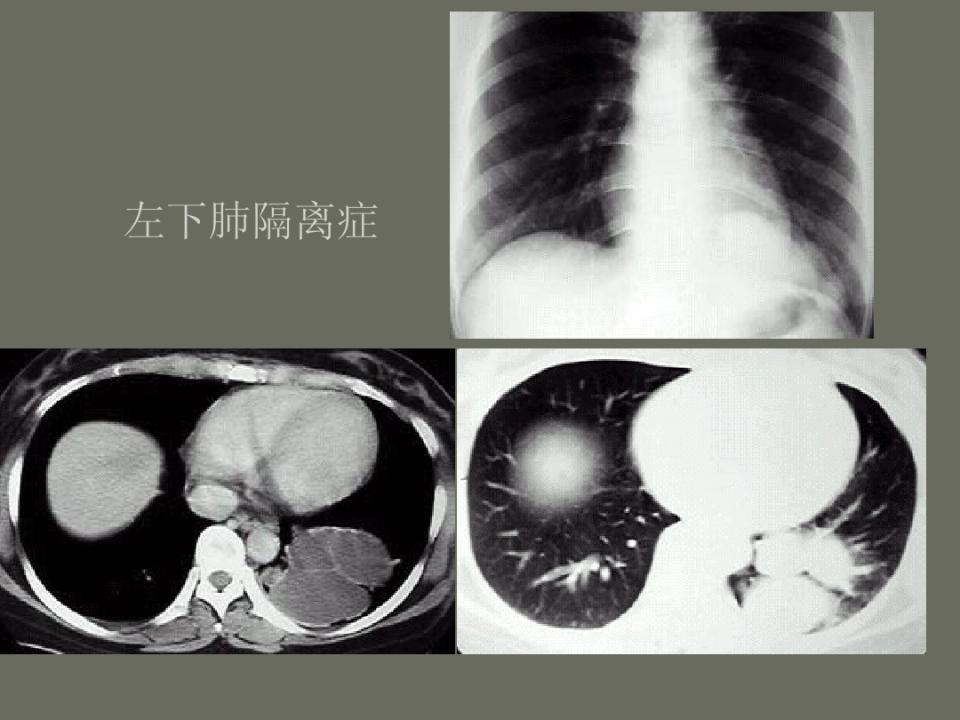

肺部先天性疾病的影像诊断